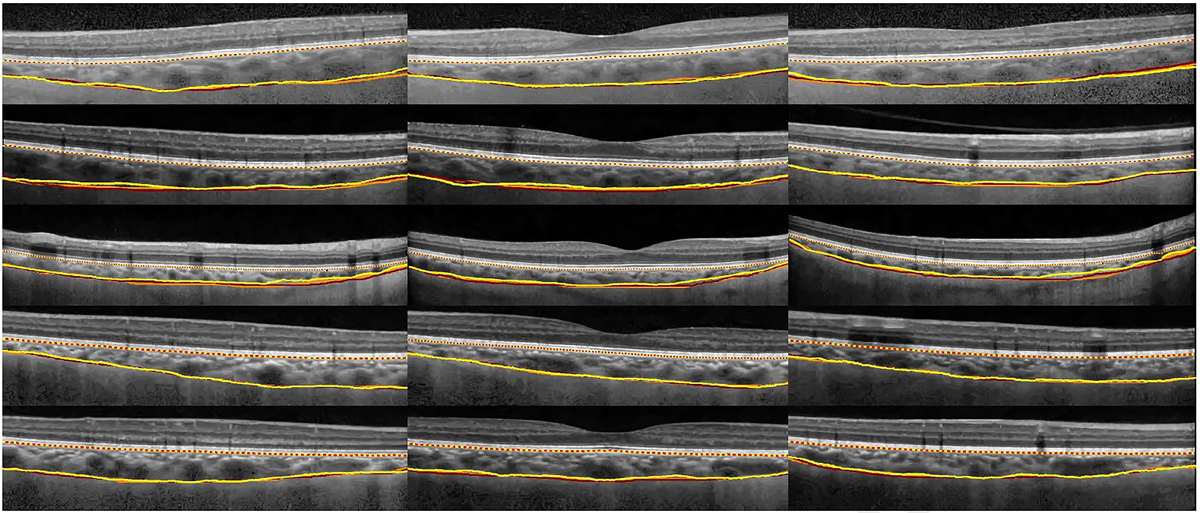

In a study by Kiran Kumar Vupparaboina et al. tensor voting, structural similarity index, and eigenvalue analysis of the Hessian matrix were used to automatically segment choroidal thickness from SD-OCT images. Manual and automated segmentation results on 485 B-scans, matched visually. Moreover, the correlation between automated and manual method was greater than 99.6%. As shown in Figure 5, the results of automated choroidal volume estimation were in close agreement with that of manual methods. The proposed method was evaluated on a large dataset from the adult population with high correlation with manual segmentation and high repeatability, but it takes more evaluation time where tensor voting accounts for about 70% of the computation [ 59 ].

Figure 5. Yellow refers to automated segmentation; orange and maroon refer to two manual segmentations (8 bit image). Reprinted from; Vupparaboina KK et al, Comput Med Imag Graph. 2015;46:315-27. Copyright (2021), with permission from Elsevier [ 59 ].